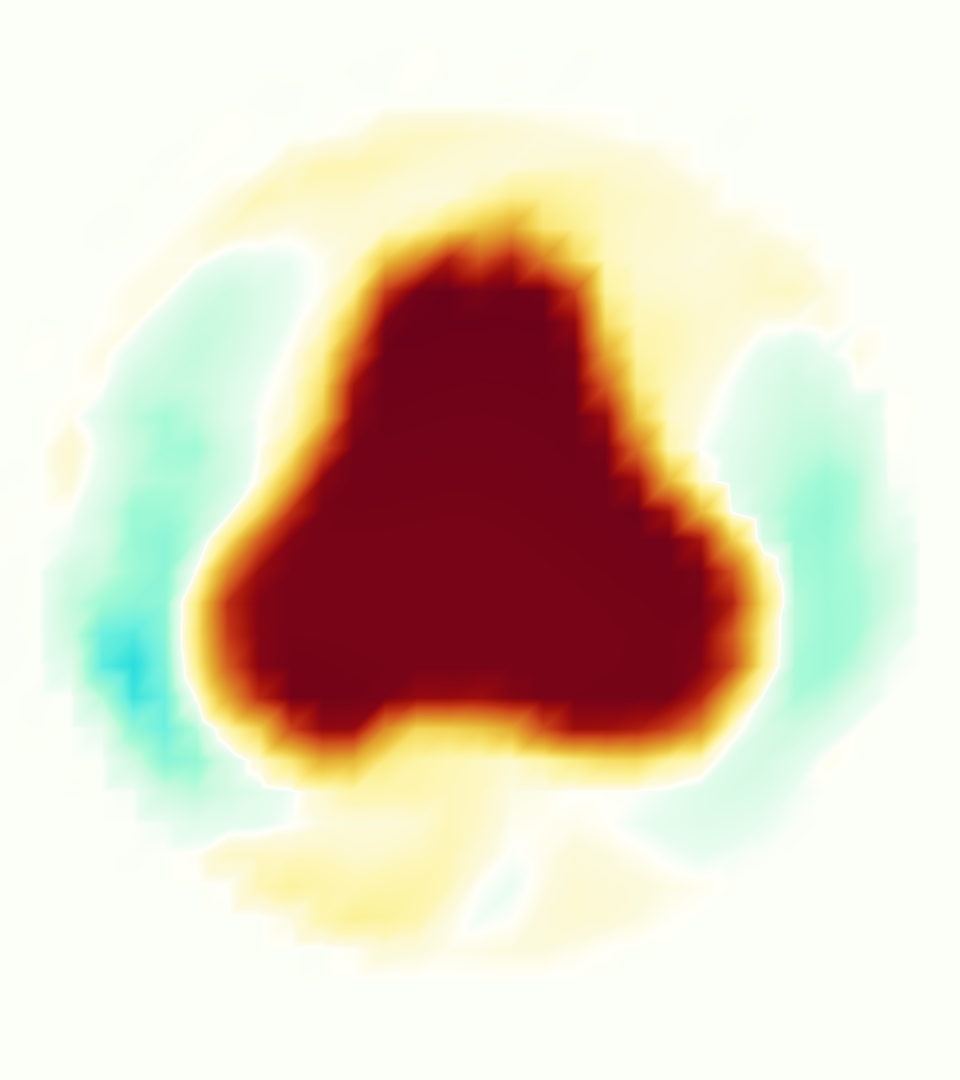

The emergent hemodynamics showed excellent qualitative agreement with experiments. Slice views of the axial component of fluid velocity ( component) in the sagittal plane that cuts through the center of the vessel, parallel to the flow direction, are shown in Figure 5. The flow in both the simulation and the experiment began to accelerate at the same time, with a jet forming through the open valve leaflets. The velocity, angle, and shape of the jet agreed well between the two cases during systole. The simulation captured the slight upward angle of the jet, which was not fully centered in the vessel. It also matched the location where the jet impacts the wall and the slower speed of the jet as it turns with the MPA downstream. As the flow decelerated, the fluid along the interior curve of the vessel reversed first while forward flow persisted where the jet was strongest, as seen in both the simulation and experimental results.

In both the experiment and the simulation, a separation region of reverse flow developed along the interior curve of the vessel under the core jet through the valve. The reverse flow began to develop at the same time in the cardiac cycle and grows throughout systole. The simulation lacked reversed flow in the entire region where reversed flow was present in the experiment, but this region developed some flow separation and had much slower flow than elsewhere in the vessel. Thus, the simulation captured that this is a distinct region from the core jet through the valve opening. There was a smaller amount of slower and slightly reversed flow along the outer curve of the vessel, close to the valve annulus and scaffold support. This region was well-matched between the experiment and the simulation.

Slice views of the (axial) component of fluid velocity in the axial plane, orthogonal to the flow direction, show that the simulation replicated the development of the jet over the cardiac cycle. At each phase, the simulation matched the forward speed of the core of the jet and the locations of reverse flow back towards the valve annulus. While there are some differences in the shape of the jet at certain phases and locations, the simulation clearly produced the general dynamics of the cardiac cycle that are seen in the experiment.

At = 0, the axial slice directly at the valve annulus shown in columns 1 and 2 in Figure 6, there was excellent agreement between the simulation and experiment over the cardiac cycle in the speed and shape of the jet through the valve. In both cases, the axial velocity increased as the flow accelerated during systole and the valve leaflets opened, then decreased during diastole with slight negative velocity before the valve leaflets were fully closed. The forward flow through the valve annulus did not form a full circle, but rather developed a triangular shape with a point of the triangle forming along the interior curve of the vessel, at the bottom of the axial slices. At = 0, the points of this triangular jet shape aligned with the commissures of the valve. This shape persisted during peak systole and was well-matched by the simulation.

The axial slice = 0.625 cm, shown in columns 3 and 4 in Figure 6, cut through the support scaffolding of the valve and the leaflets when they are open. In the experimental data, the shape of the jet changed as it moved downstream. A triangular shape occurred, but the points were then aligned with the middle of each open leaflet as opposed to the commissures. Those points were also more rounded than they were at = 0. The peak velocity of the jet was faster at = 0.625 cm than at = 0, as the flow accelerated through the open valve leaflets. The simulation produced these features at = 0.625 cm. The triangular shape of the jet shifted similarly, and its speed increased compared to the upstream slice. As the flow decelerated into diastole, the jet shape remained roughly triangular but diminished in intensity before disappearing after valve closure.

The jet continued to develop at = 1.25 cm, an axial slice immediately downstream of the valve scaffolding and open leaflets, shown in columns 5 and 6 in Figure 6. In the experimental data, the points of the triangular jet shape extended further towards the vessel wall. In addition, regions of reversed flow developed in the locations downstream of the commissures, resulting in curved sides to the shape of the jet. Each tip of the jet was unique, due to variations in the individual leaflets in the physical bioprosthetic valve. These variations are apparent in the velocity fields, possibly because the jet edges are similar enough cycle to cycle that irregularities are still being captured even with phase averaging. Further discussion of these features can be found in Schiavone et al. [39], which showed that the jet tip shapes occurred in different pulmonary anatomies, demonstrating that they were likely due to inherent properties of each leaflet. The leaflets in the mathematical model of the valve are identical, so these nuances in leaflet variation could not be replicated. The simulation did capture some of the extension of the tips of the jet, as they were closer to vessel wall at slice = 1.25 cm than = 0.625 cm. The curves in the triangular sides of the jet were also present in the simulation, though they were less pronounced than the experimental data. At both = 0.625 cm and = 1.25 cm, the jet shape in the simulation was smoother than the jet in experiment. It is possible that the free edges of the leaflets in the mathematical model are not fully replicating the behavior of the physical leaflets of the bioprosthetic valve, in particular the amplitude or frequency of leaflet flutter, leading to the variations seen in the jet shape at = 1.25 cm downstream of the leaflet edges. The simulation, however, does capture the key features of the triangular shape and speed of the jet. Overall, qualitative comparisons demonstrated that the simulation reproduced key features of the flow during systole and diastole.